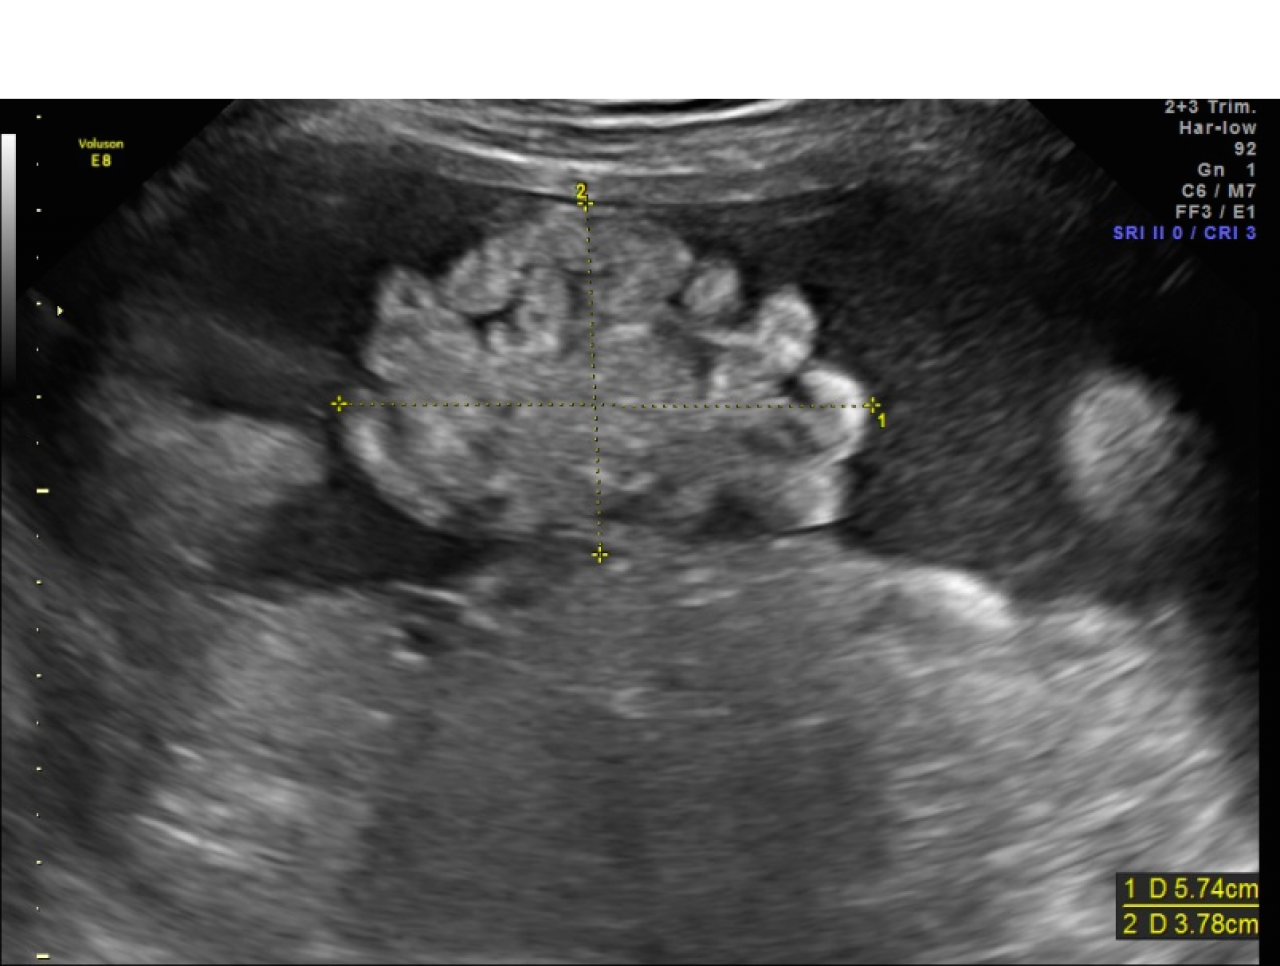

From radiopaedia.org

Gastroschisis Image What Is Gastroschisis gastroschisis is a paraumbilical abdominal wall defect associated with protrusion of the bowel through the defect. A membrane does not cover. gastroschisis is a birth defect in which the baby's intestines extend outside of the abdomen through a hole next to the belly. Learn about the causes, symptoms, diagnosis, and treatment of gastroschisis and how it affects your. What Is Gastroschisis.

Gastroschisis Image What Is Gastroschisis A membrane does not cover. gastroschisis is a paraumbilical abdominal wall defect associated with protrusion of the bowel through the defect. gastroschisis is a birth defect that causes intestine and other abdominal organs to protrude through a hole in the abdominal wall. gastroschisis is a condition where the intestines extend outside of the body through a hole. What Is Gastroschisis.